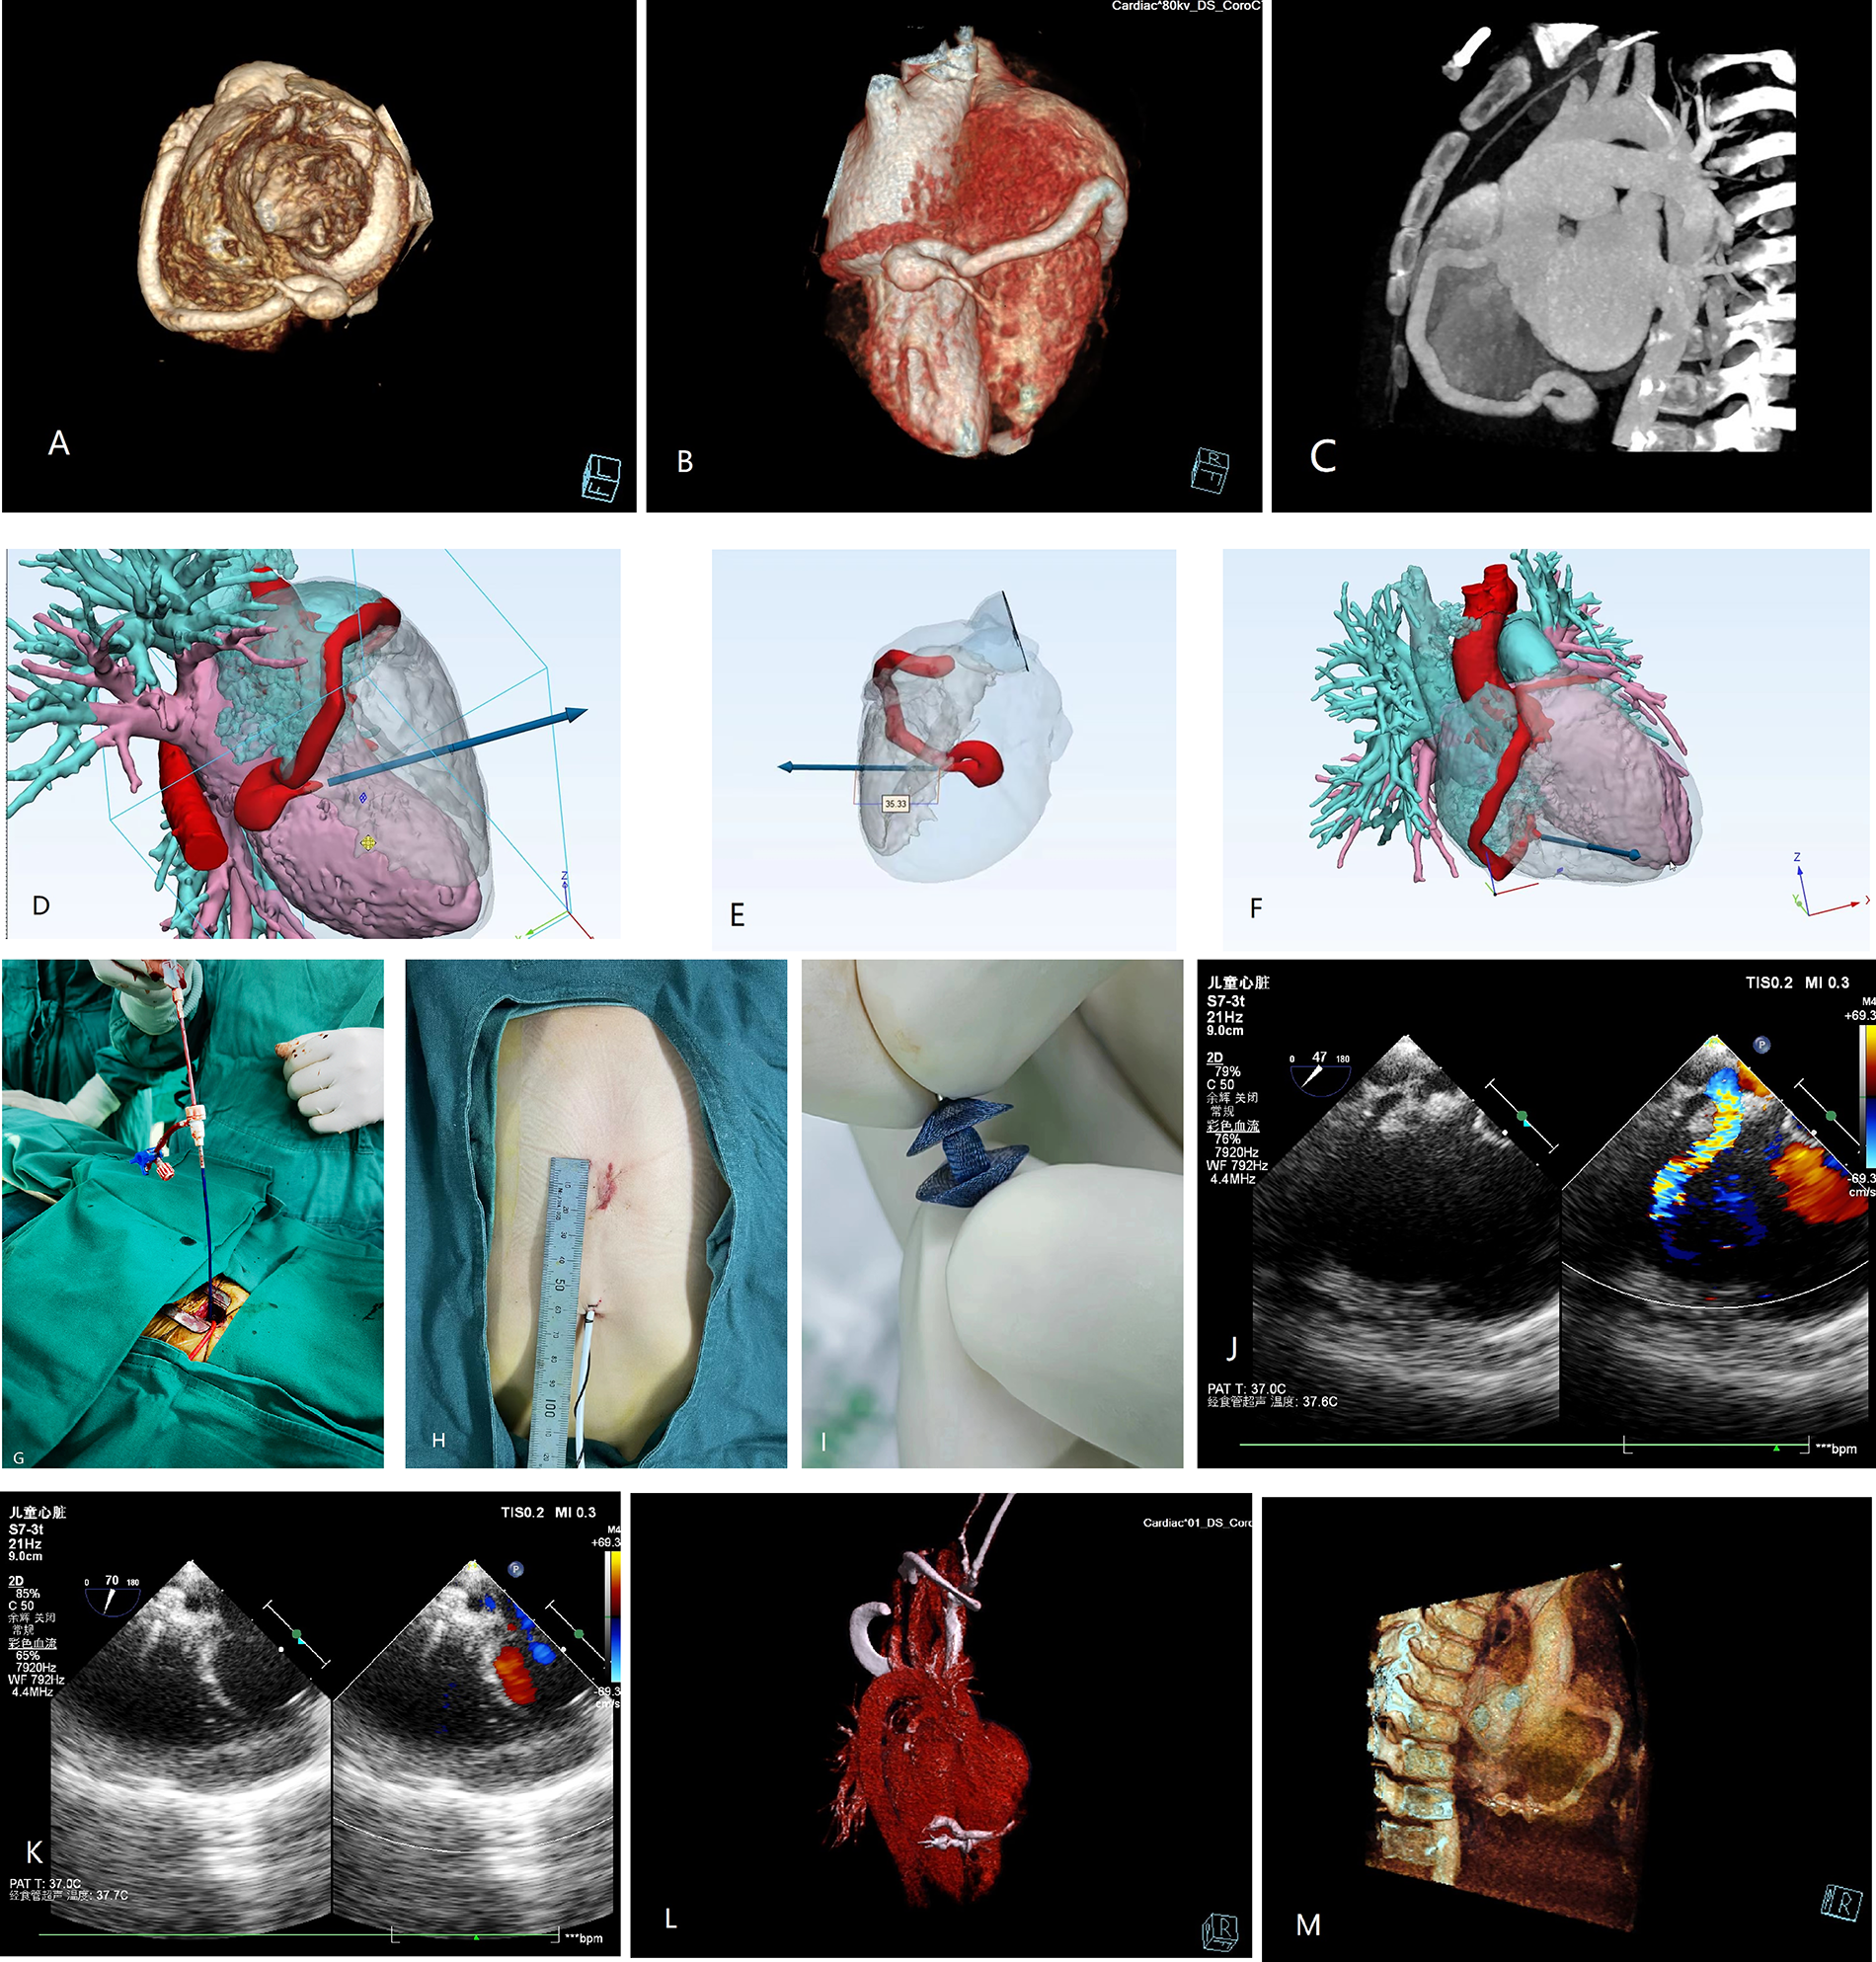

A 2.8-year-old boy was referred to our institution for a grade III/IV systolic heart murmur detected during a physical examination for pneumonia. Echocardiography revealed slight enlargement of the left heart and dilation of the right coronary artery (RCA), with an internal diameter of approximately 5 mm. A 4 mm CAF was observed in the apical part of the right ventricle (RV), with a left-to-right shunt, and a maximal continuous flow velocity of 4.4 m/s. Cardiac computed tomography angiography (CTA) (Figure 1A–C) confirmed that the RCA was dilated giving birth to a CAF extending from the atrioventricular groove to the base of the heart, making a 360° rotation before draining into the RV, with a posterior descending branch evident at the lateral wall of the fistula. Preoperative simulation using computer-based 3D imaging (Figure 1D–F) was performed to determine the puncture site on the right ventricular free wall, as well as the sheath direction and insertion depth. The case was discussed during a multidisciplinary meeting and a decision for elective minimally invasive hybrid surgery was taken at the age of 3.8 years old (15 kg/100 cm).

Preoperative 3D (A,B) and 2D (C) computed tomography (CT) images. (D–F) 3D images simulating the fistula drainage position and allowing reverse extrapolation of the puncture site and depth on the right ventricular free wall. (G) Surgical procedure. (H) Access incision. (I) Occluder. (J,K) Intraoperative ultrasound image for identifying the direction of blood flow and determining the direction of sheath guidance. Postoperative 3D (L) and 2D (M) CT images of the successfully occluded coronary artery fistula.

After obtaining the parents' consent, the procedure was undertaken in the operating theater under transesophageal echocardiography (TEE) guidance. After systemic heparinization and antibiotic prophylaxis, a 2 cm incision was made at the inferior medial end of the sternum, with dissection of the inferior sternum layer by layer. The pericardium was incised and suspended to expose the anterior wall of the RV. The puncture site was identified using a combination of preoperative 3D imaging and intraoperative TEE (Figure 1D–F, Figure 1J–K). A purse-string suture was placed at the puncture site, followed by puncture and insertion of the guidewire (4-F) and sheath (1.17 mm). The TEE operator guided the sheath into the fistula, and a 4 × 4 mm Amplatzer Duct Occluder II (ADO II) (Abbott, USA) was inserted along the sheath until it was implanted. The occluder was released after a multi-view ultrasound confirmed no residual shunt or abnormalities (Figure 1G–K). The procedure lasted 30 min. The patient was extubated on the first postoperative day and discharged on the fourth postoperative day under oral heparin. Repeat examinations showed normal results (Figure 1L, M). Follow-up at 1 month, 2 months, 6 months, and 1 year revealed the occluder was well-positioned with no significant abnormalities observed.